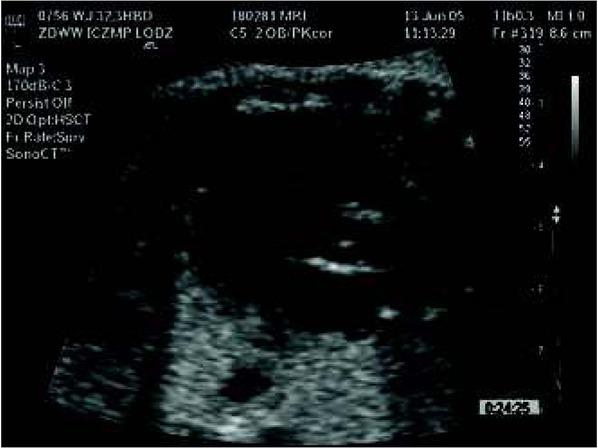

Fig. 4